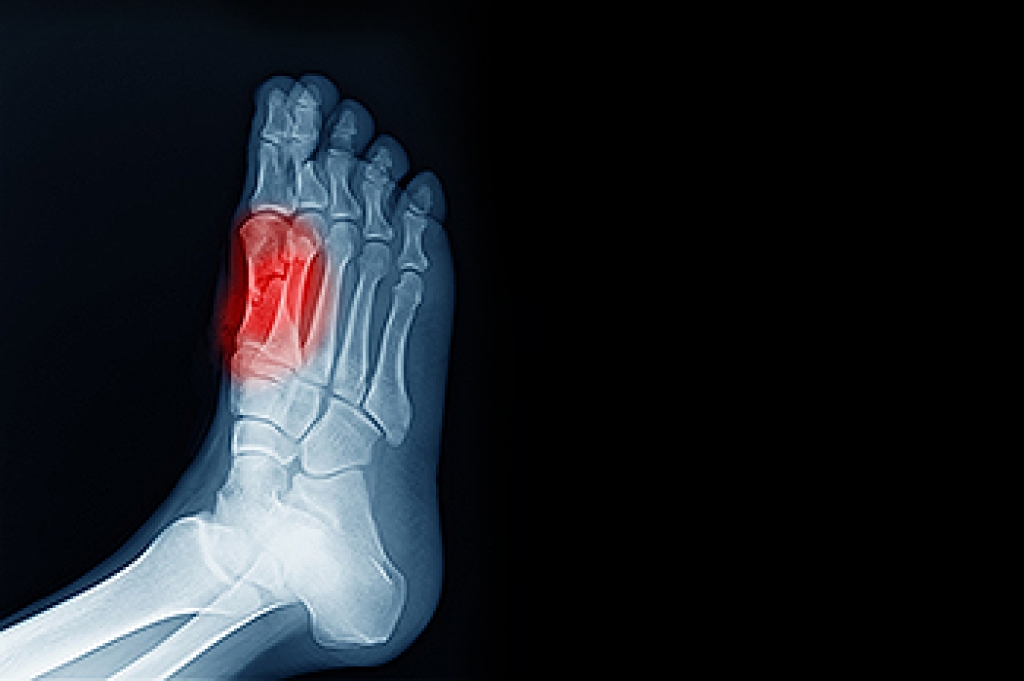

Working on your feet for long hours can lead to a variety of foot-related issues. The constant stress on the bones, muscles, and tendons can cause inflammation, pain, and even permanent structural changes. The foot's arches, which normally act as shock absorbers, may weaken due to prolonged standing or walking, leading to flat feet. This loss of arch support can affect not only the feet but also the knees, hips, and lower back, making them more vulnerable to injury. Painful foot conditions related to working on the feet include plantar fasciitis, Achilles tendonitis, and bunions, all of which may worsen with time. Symptoms like fatigue, pain, and discomfort often spread from the feet to the legs and back, making it difficult to continue standing or walking for extended periods. If you have foot pain related to working on your feet, it is suggested that you make an appointment with a podiatrist for an exam, diagnosis, and treatment options.

Standing on your feet for long periods of time can cause stress and pain in your feet. Your whole body may experience change in terms of posture, back pain, bunions, callouses and or plantar warts. There are ways to avoid these conditions with proper foot care, smart choices and correct posture.